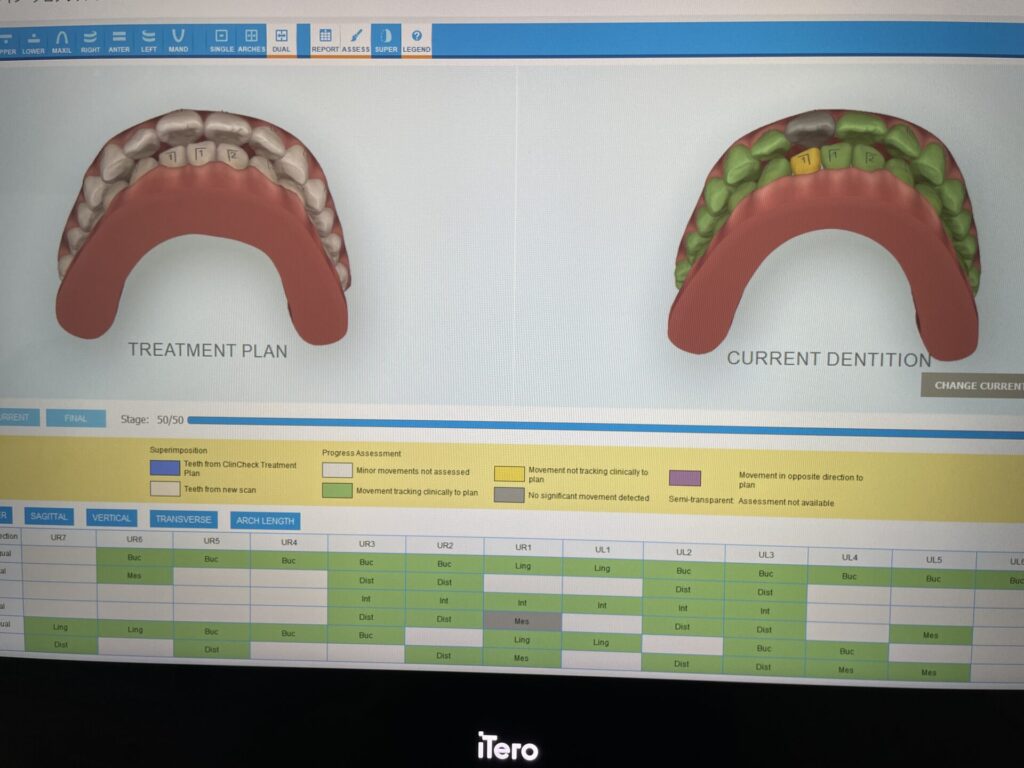

インビザラインで抜歯矯正を計画しました。枚数は50枚 期間はおよそ1年半のプランです。

矯正前はもちろん矯正期間中の定期検診でも毎回お口の中をスキャンします。当院のスキャナーは近赤外線を使って被曝なしで虫歯を検知できます。また矯正プランとのズレも評価できます。